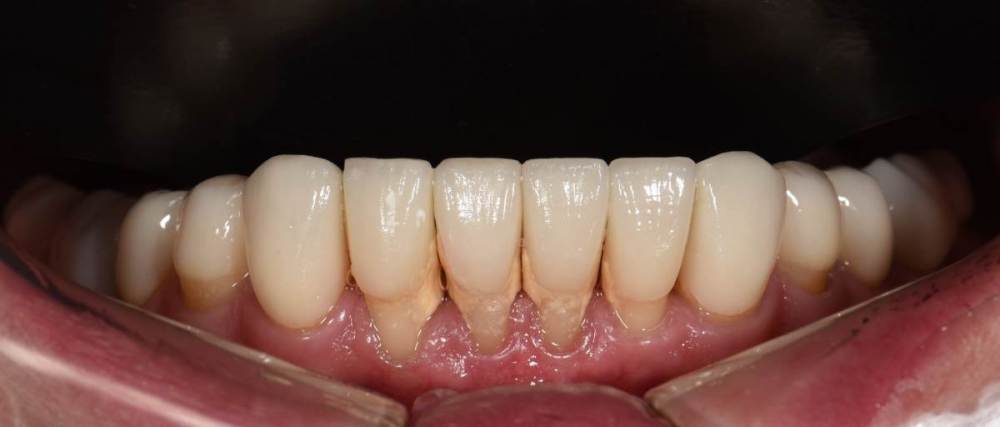

Финал работы:

DSC_3144.thumb.JPG.c9e60b8847f66dc01ba0e6e1113ab39b.JPGDSC_3145.thumb.JPG.1723748a079bc482f1a7e4534aff8f33.JPGDSC_3146.thumb.JPG.6dd4d0eb29dc3e6e92773c3c7892f692.JPGDSC_3147.thumb.JPG.e4f9cc2d841e3b7ff3aa73491ba9b4a3.JPGDSC_3148.thumb.JPG.0f174600adf2a49d65266a0ff665abfd.JPGDSC_3149.thumb.JPG.c9849be795d45b2573488d4545f3843f.JPGDSC_3150.thumb.JPG.6380366ecde7802fa32c6471b8b33883.JPGDSC_3153.thumb.JPG.1420d109d08ed1d6bd63447fe73eeed6.JPGDSC_3154.thumb.JPG.04b902149b3c0f9f2f1bcfa2e310c855.JPG

Фото спустя месяц после фиксации. Сначала нижняя челюсть, потом верхняя. Решение с передними нижними зубами - компромиссное. Все они витальные, имели 2-3 степень подвижности. После исправления положения нижней челюсти и установления правильных окклюзионных контактов - 1-2 степень подвижности. По поводу гигиены пытаемся.